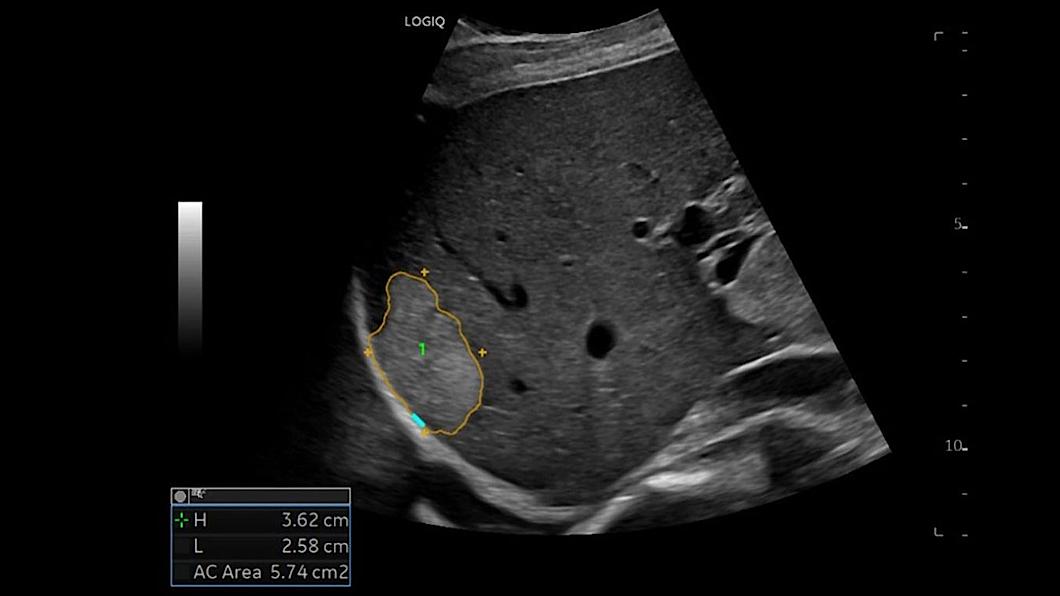

L'échographie de contraste (CEUS)

Aide les cliniciens à visualiser clairement la structure des tissus et la vascularisation des lésions pour une détection et une caractérisation plus fiable de celles-ci.